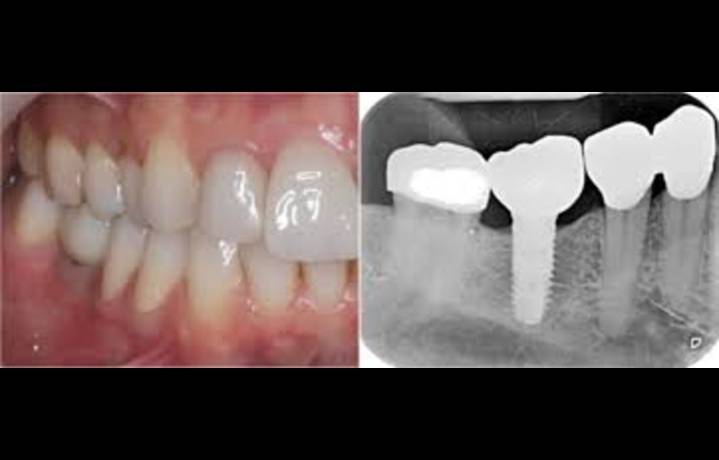

Researchers have found in a new study that the intermediate abutment-healing cap system appears suitable for single implant intraoral scans, providing clinically acceptable levels of scanning accuracy. The study evaluated multiple intraoral scanners and found that all devices achieved acceptable trueness when used with the intermediate abutment-healing cap system. Among the scanners tested, the Dexis IS 3800 demonstrated higher precision, indicating more consistent reproducibility. These findings suggest that the intermediate abutment-healing cap system can facilitate accurate digital impressions and may improve workflow efficiency in clinical implant dentistry. While promising, the authors recommend further validation through in vivo studies to ensure consistent performance under real cli

Intermediate Abutment-Healing Cap System Ensures Accurate Single Implant Scans, suggests study